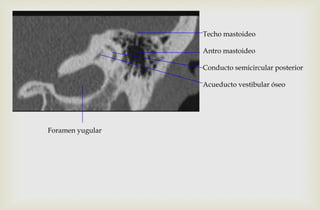

Techo mastoideo

Antro mastoideo

Conducto semicircular posterior

Acueducto vestibular óseo

Foramen yugular